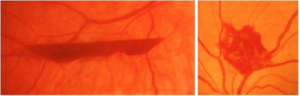

视网膜前出血与玻璃体积血

视网膜前出血

视网膜前出血(PRH)位于视网膜前部,可有液平面或呈近似圆形、连续或线性片状出血。

脱离的视网膜表面的出血也被认为是视网膜前出血。

玻璃体积血

位于玻璃体腔内的出血(比视网膜前出血位置更靠前)被称为玻璃体积血(VH)。

当存在晶状体混浊或对焦不良时,阅片医生可能难以对玻璃体出血的情况进行准确判断。

▲ 视网膜脱离

▲ 视网膜前出血(PRH)可见于视网膜脱离的表面。